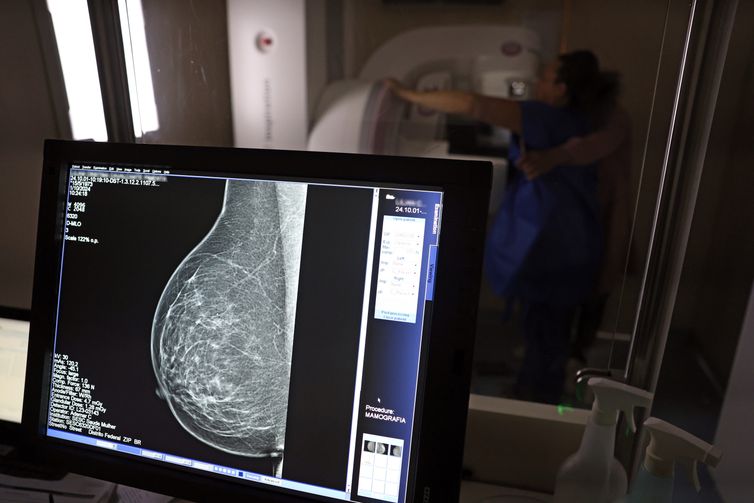

Câncer de mama é uma das doenças que mais afetam mulheres no Brasil, impactando não apenas a saúde física e emocional, mas também a capacidade de trabalho e a segurança financeira das pacientes.

© José Cruz/Agência Brasil

No Outubro Rosa, o Instituto Nacional de Câncer (Inca) estimou 73.610 novos casos este ano no país. É o câncer que mais mata mulheres no Brasil. As mulheres em tratamento pela doença têm o direito de receber o auxílio-doença ou o benefício de prestação continuada.